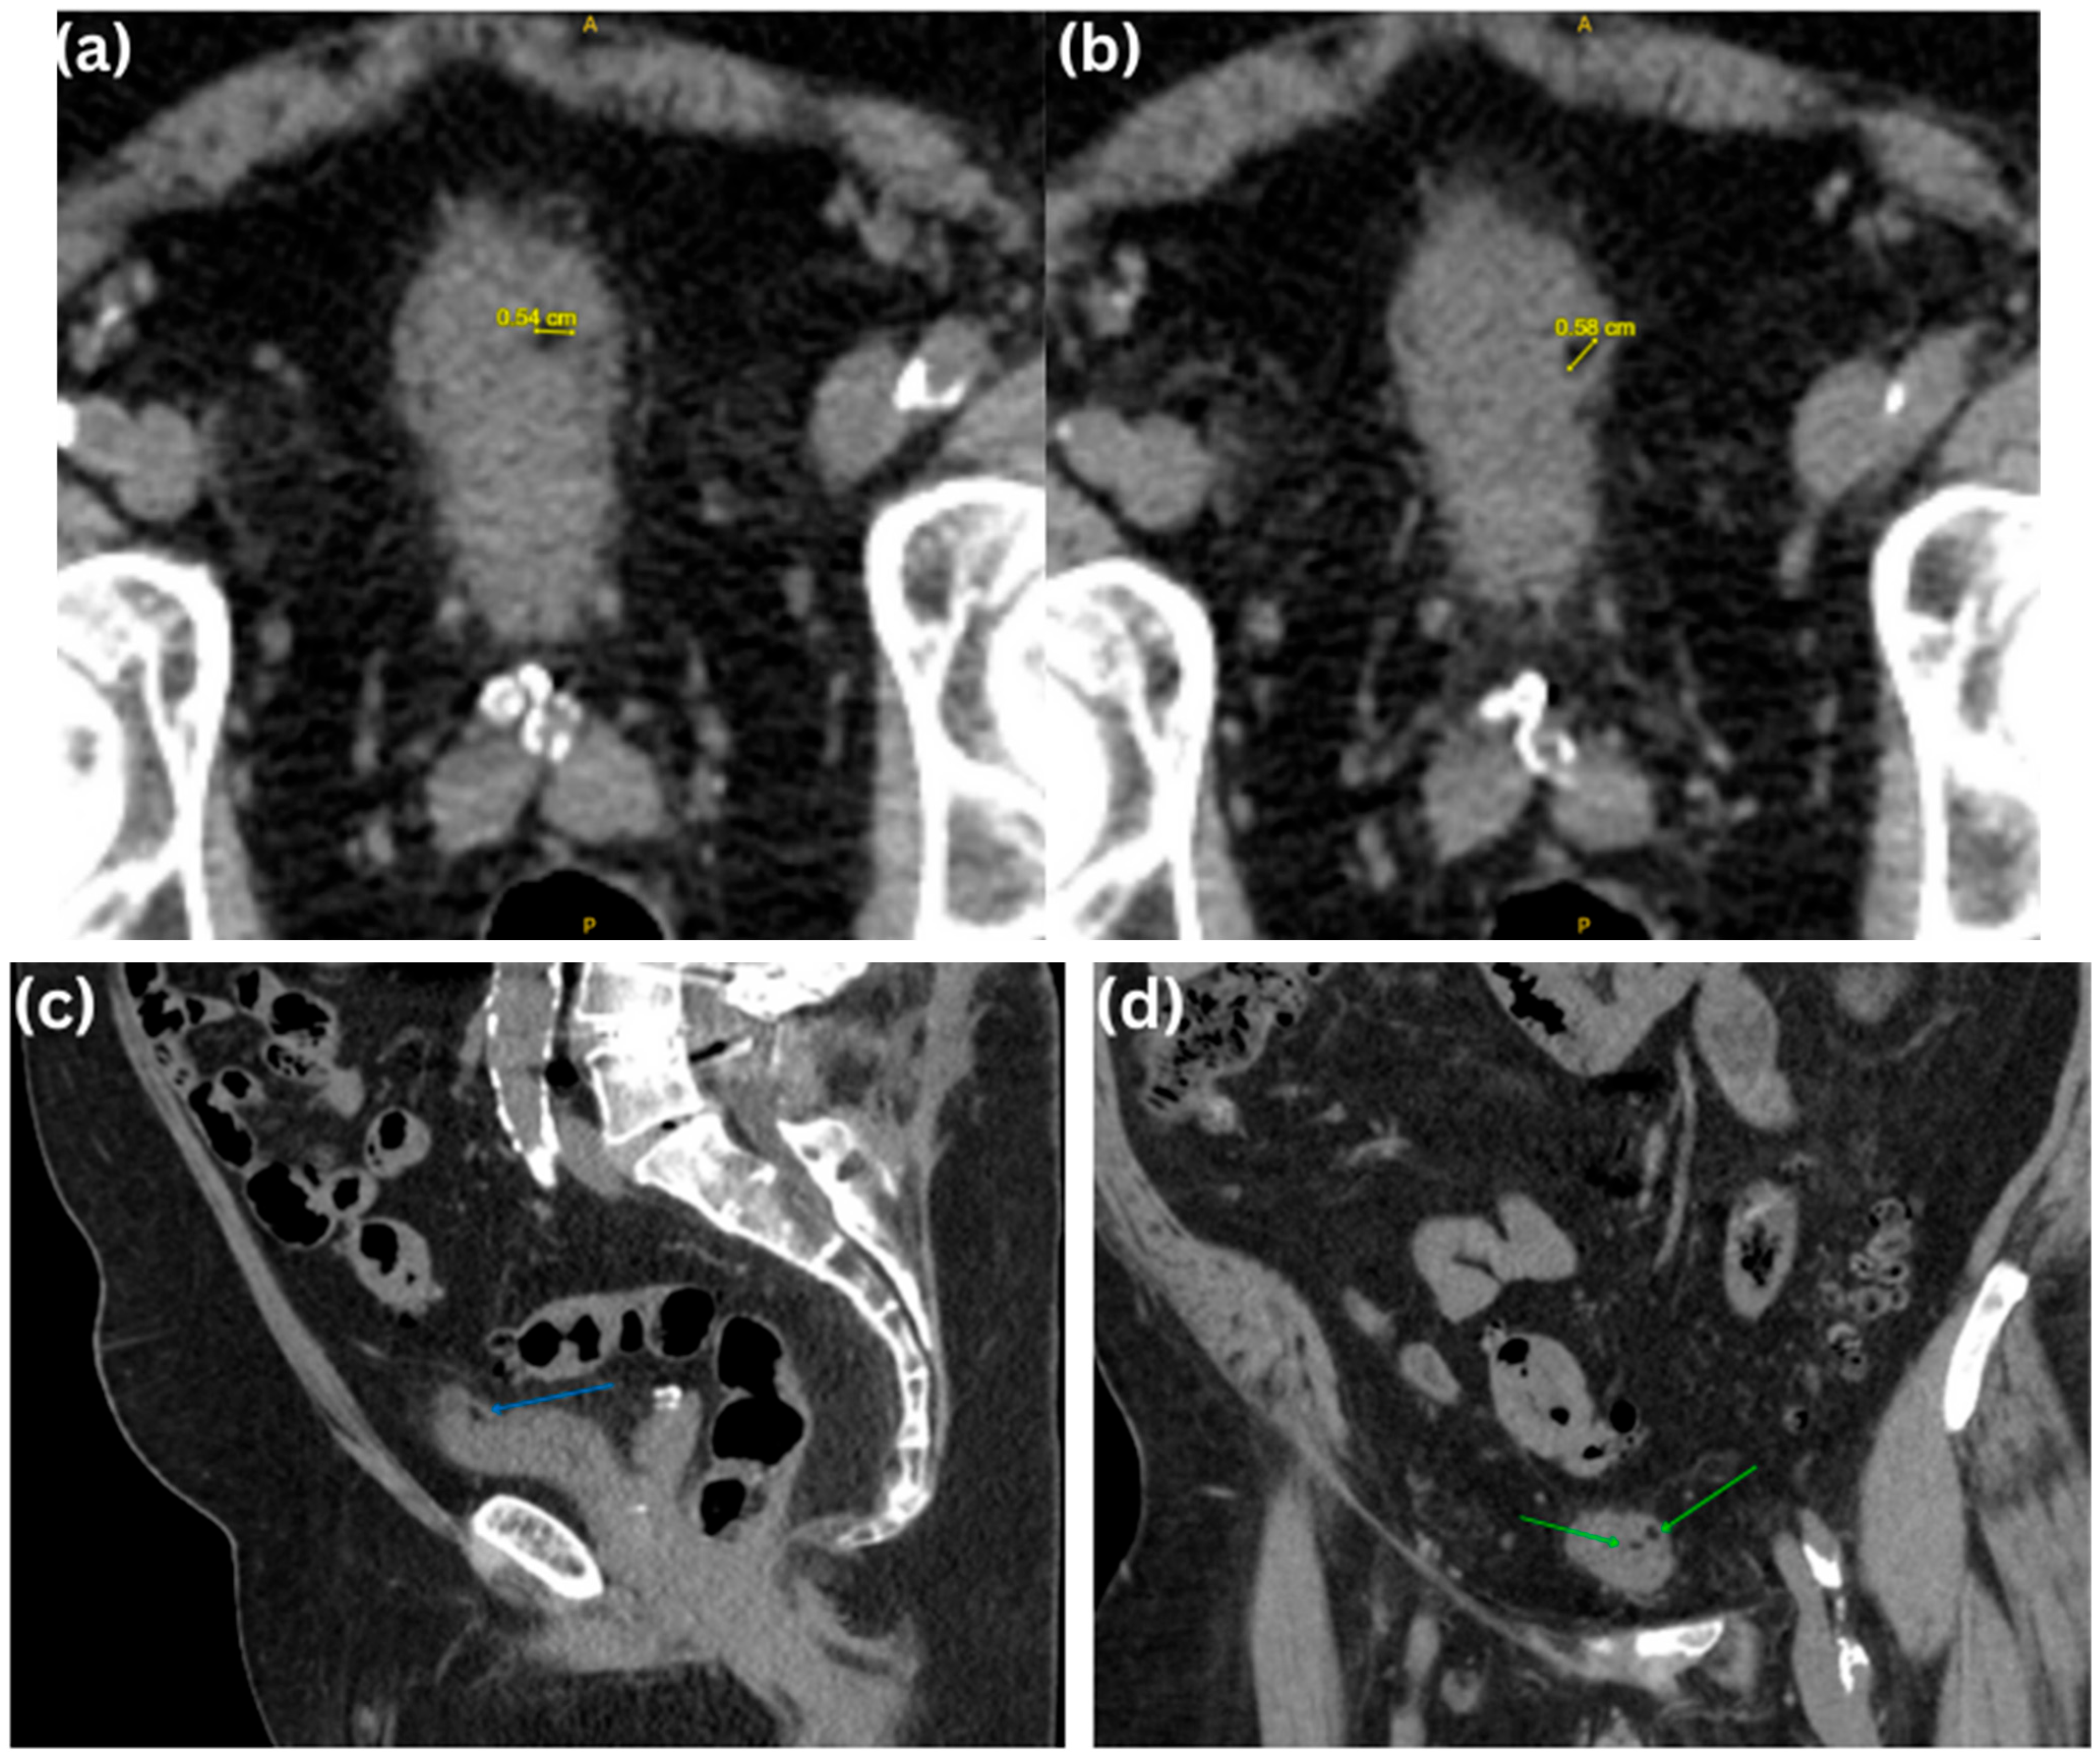

| CT | Homogenous, endophytic, hypodense lesion with smooth margins as viewed in the non-enhanced, venous, or excretory phase (Figure 2). Fat attenuation of the lesion ≤ −20 HU, which is diagnostic of lipoma (usually −50 to −150 HU). | -Erich K. Lang et al. reported that in an excretory phase CT generating 5 mm thick slices demonstrated 7 to 9 mm grape-like lesions, with attenuation coefficient ranging from −60 to –160 HU found in the trigone region [14]. -The presence of septations as reported by Paniagua et al. (Figure 5) raised suspicion of malignant liposarcoma, which would require surgical intervention [22]. |

| US | Fatty composition showcasing homogenous, hyperechogenic lesion with endophytic growth.(Figure 7) | -Echogenicity could be very similar to the fat around the bladder, as observed by Paniagua et al., potentially mimicking an extravesical lesion pushing into the bladder (Figure 5) [22]. -In Ukita S et al.’s case of a retropelvic lipoma, TVUS revealed an echogenic mass in the right adnexal region, suggesting a mature ovarian cystic teratoma congaing fat. MRI and surgery were required for confirmation and treatment [16]. |